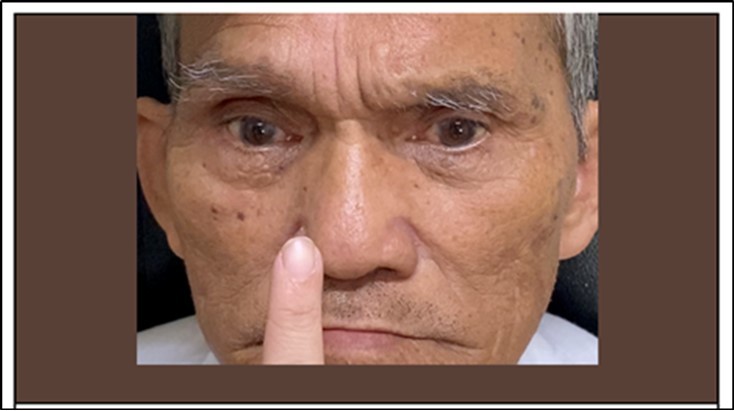

The patient was then referred to the Ophthalmology Service at the ER level. At that time the VA of the patient was 6/10 on both eyes, unremarkable anterior segment findings with an NO4 NC4 cataract for both eyes and unremarkable funduscopic findings.Patient had bilateral exotropia in primary gaze with the pupillary light reflex on the nasal limbus of both eyes on Hirschberg. (Figure 1). Patient had bilateral adduction deficits in both version and duction tests.Other cranial nerves were intact.

Figure 1.Bilateral exotropia on primary gaze exotropia and bilateral adduction deficit during version

The patient was referred back to Ophthalmology service after 4 days. The patient was conscious, coherent, oriented to three spheres, wheel chair borne. At this time, there was persistence of diplopia but there was no dizziness. The BCVA of the patient was 6/7.5 both eyes. Ishihara was 14/15 for both eyes, with persistent bilateral exotropia in primary gaze. Exotropia was measured at 30 prism diopters on Krimsky and unchanged bilateral adduction deficits in both version and duction tests. (Figure 4)

Horizontal nystagmus of the abducting eye and gaze evoked vertical nystagmus on both eyes were noted. (Video 1 and 2) The adduction deficit was not overcome with either doll’s head maneuver and with an accomm dating target. (Figure 5) Forced duction testing was done and there was no restriction on both eyes noted.